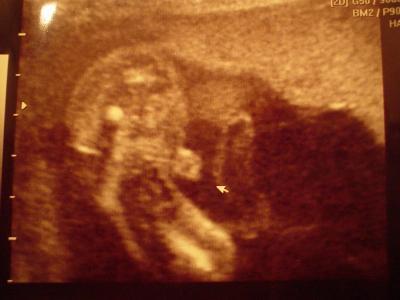

Outingbild aus 22.woche,was denkt ihr?

Ich seh da eindeutig den Hodensack mit einem Pipimatz! Also ein JUNGE!!! Jippieee, Jungs sind sowas von klasse!!!

Mir wurde gesagt es sieht zu 80%Nach Junge aus,....ein paar minuten später sagte sie das sie auch die hoden sehen kann:-))